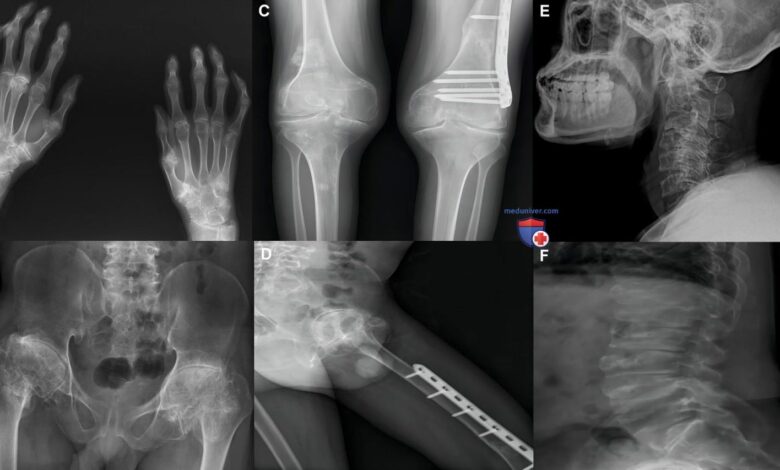

Для предотвращения проблем с коленными суставами важно регулярно проходить профилактические осмотры у врача-ортопеда. Раннее выявление проблемы позволяет своевременно начать лечение и избежать серьезных осложнений.

При возникновении болей или дискомфорта в области коленей необходимо обратиться к специалисту для диагностики и определения дальнейших шагов по лечению. Не стоит откладывать визит к врачу, так как вовремя начатое лечение обеспечивает быстрое восстановление.